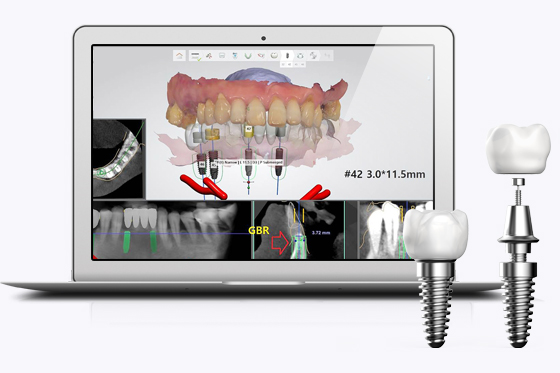

철저하고 정확한 준비

한 번 잘못 심어진 임플란트는 바로 잡기가 매우 어렵습니다. 솔트 치과는 수술 전 3D CT와 디지털 구강스캔 후 임플란트 식립 위치를 잡고, 수술 시 네비게이션 가이드로 안전하게 위치시킵니다.